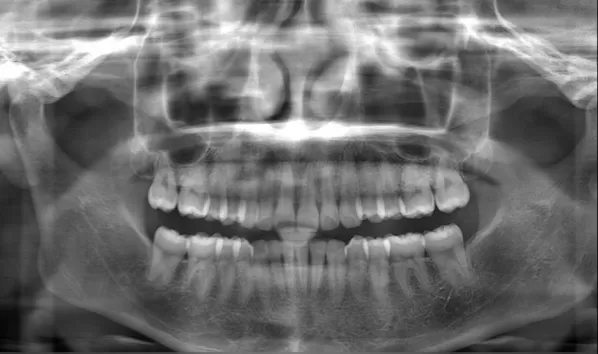

Rayons X avant le traitement

[Radiographie panoramique/Céphalogramme latéral]